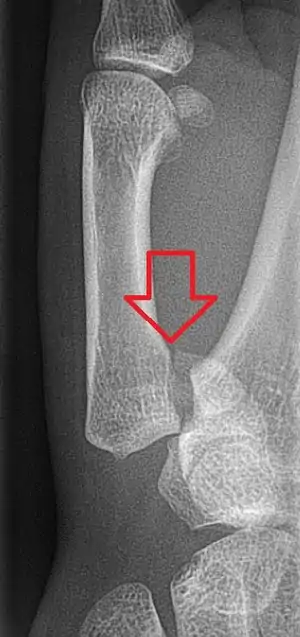

Bennett fracture is a type of partial broken finger involving the base of the thumb, and extends into the carpometacarpal (CMC) joint.[1]

This intra-articular fracture is the most common type of fracture of the thumb, and is nearly always accompanied by some degree of subluxation or frank dislocation of the carpometacarpal joint.

In the case of the Bennett fracture, the proximal metacarpal fragment remains attached to the anterior oblique ligament, which in turn is attached to the tubercle of the trapezium bone of the CMC joint. This ligamentous attachment ensures that the proximal fragment remains in its correct anatomical position.

The distal fragment of the first metacarpal bone possesses the majority of the articular surface of the first CMC joint. Unlike the proximal fracture fragment, strong ligaments and muscle tendons of the hand tend to pull this fragment out of its correct anatomical position.

Specifically:

- tension from the abductor pollicis longus muscle (APL) subluxates the fragment in a dorsal, radial, and proximal direction

- tension from the APL rotates the fragment into supination

- tension from the adductor pollicis muscle (ADP) displaces the metacarpal head into the palm

Tension from the APL and ADP muscles frequently leads to displacement of the fracture fragments, even in cases where the fracture fragments are initially in their proper anatomic position. Because of the aforementioned biomechanical features, Bennett fractures nearly always require some form of intervention to ensure healing in the correct anatomical position and restoration of proper function of the thumb CMC joint.